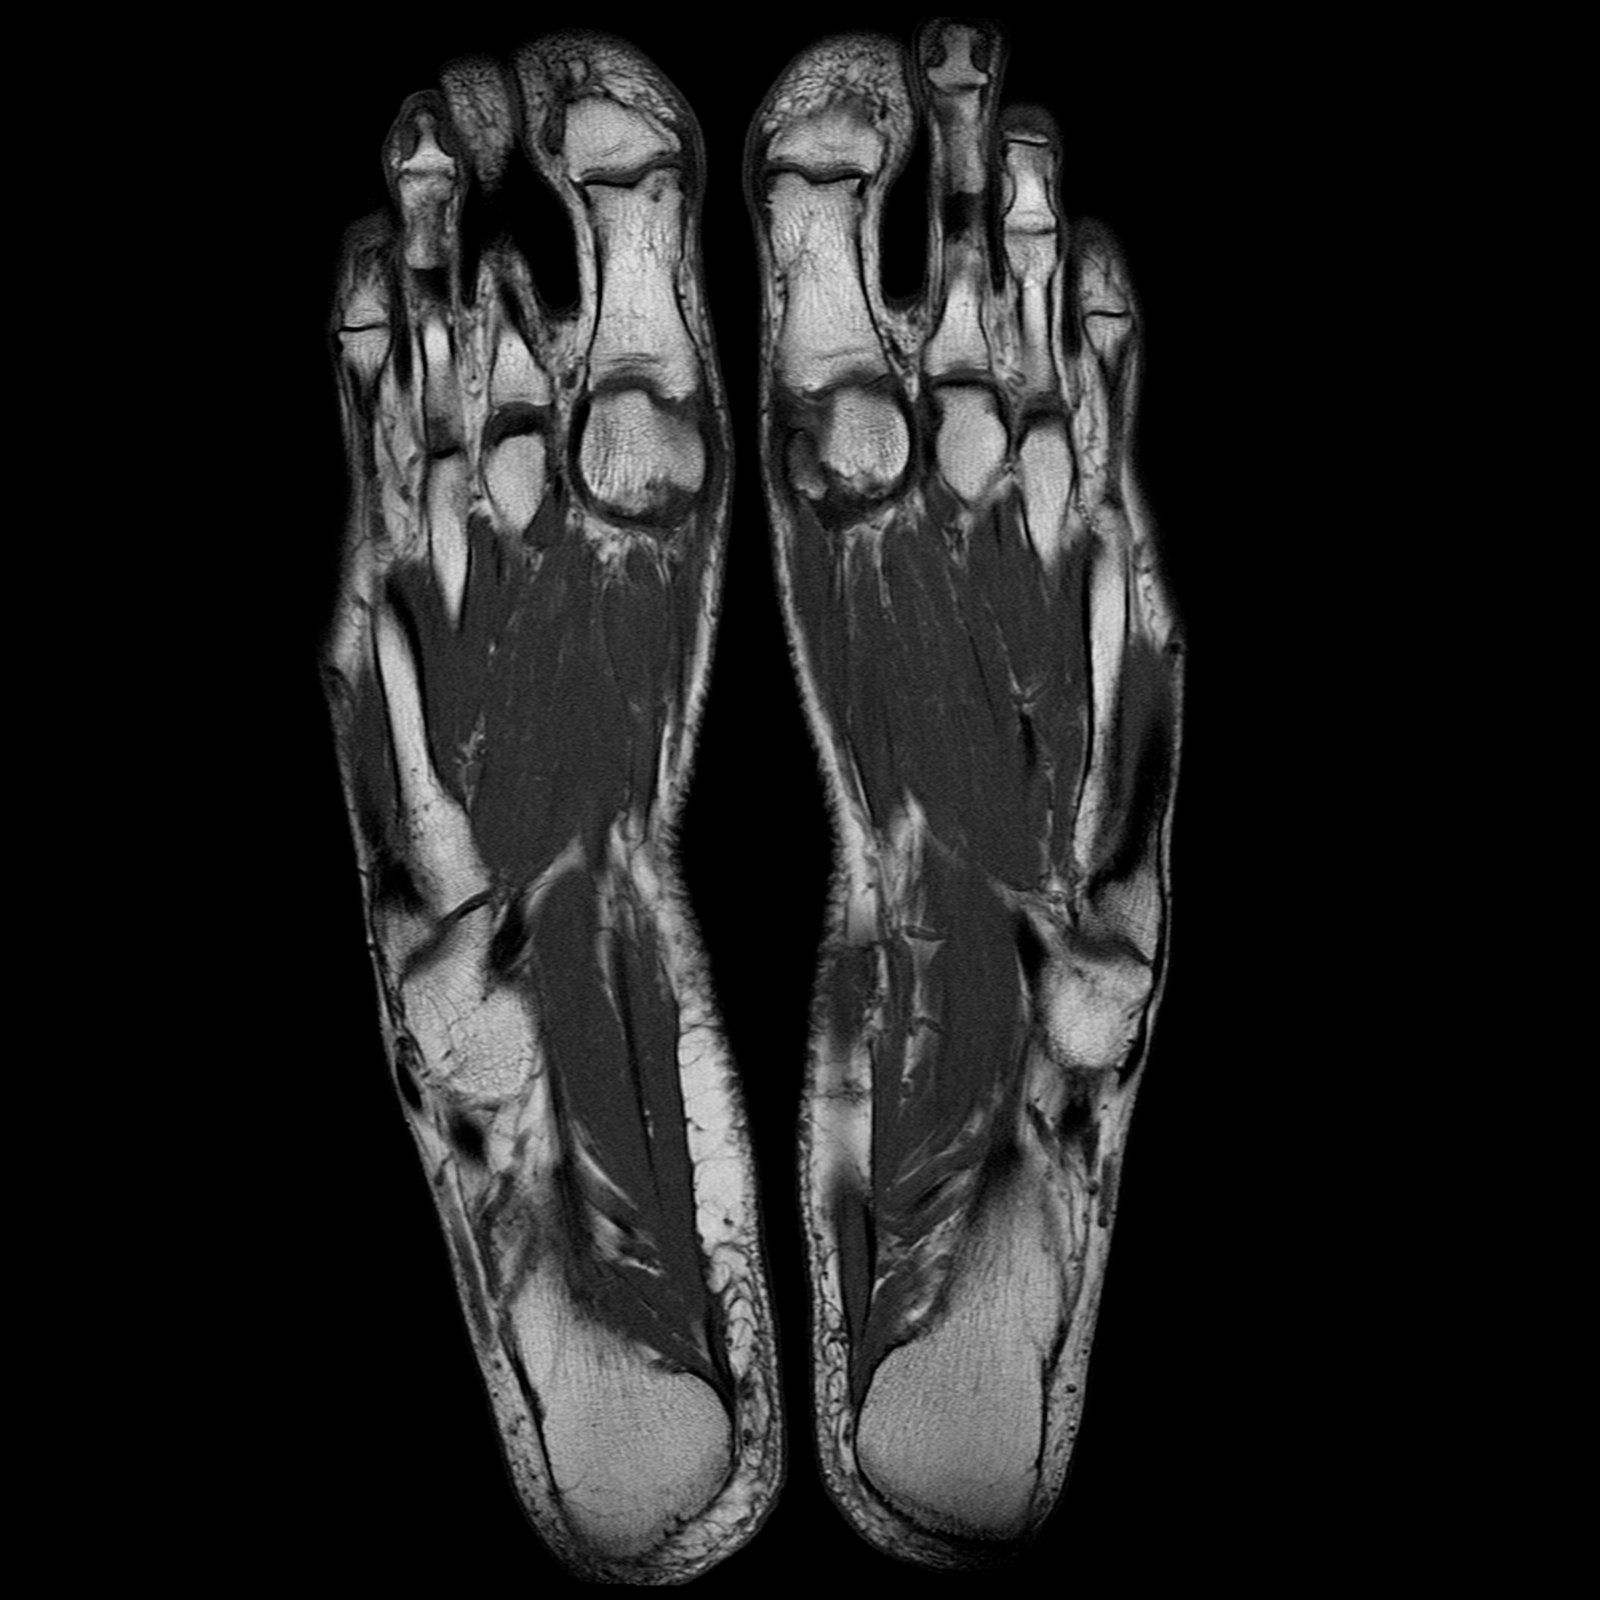

Musculoskeletal